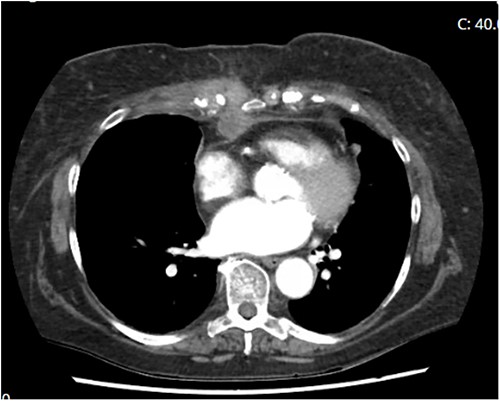

The lesion continued to grow. Blood investigations demonstrated a slightly elevated CRP (~120) and normal white cell count. Several months later, a ‘satellite’ nodule appeared inferiorly (around the xiphoid process) (Fig. 1). Contact was subsequently made with her surgeon, who organised for a in-person review. The patient was admitted directly to hospital for urgent treatment in November 2021 (Fig. 2).

Computed tomography demonstrating penetrance of infection deep to sternum.

Ms GL was diagnosed with a deep sternal wound infection. The most common infective agent implicated in DSWI is Staphylococcus (followed by Enterococcus). This atypical sternal wound infection was positive for fungal growth, specifically Lomentospora prolificans—a dangerous and resistant pathogen that affects immunosuppressed patients [2]. This was treated with a combination of voriconazole and miltofosine under the instruction of infectious disease physicians [3].